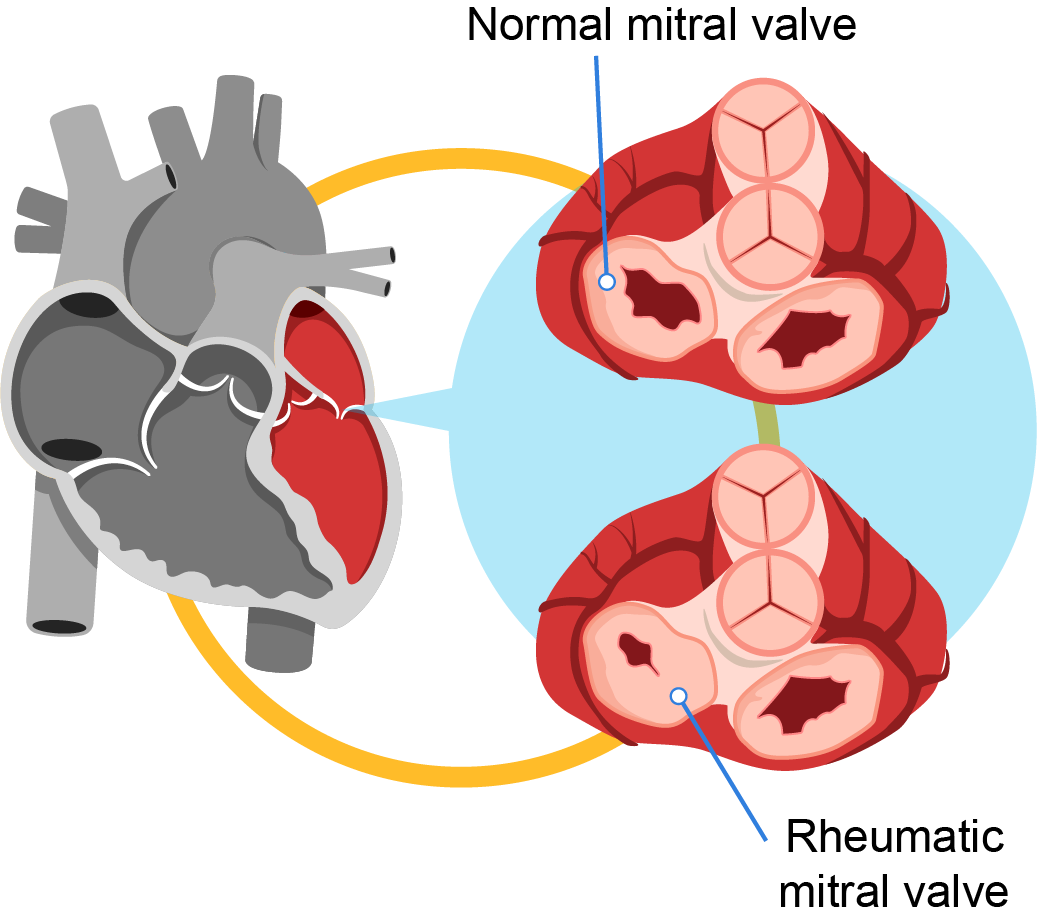

Rheumatic Heart Disease Symptoms Causes Pantai Hospital

RHEUMATIC HEART DISEASE Define Etiology Risk Diagnostic

Rheumatic Fever And Rheumatic Heart Disease

Rheumatic Fever And Rheumatic Heart Disease